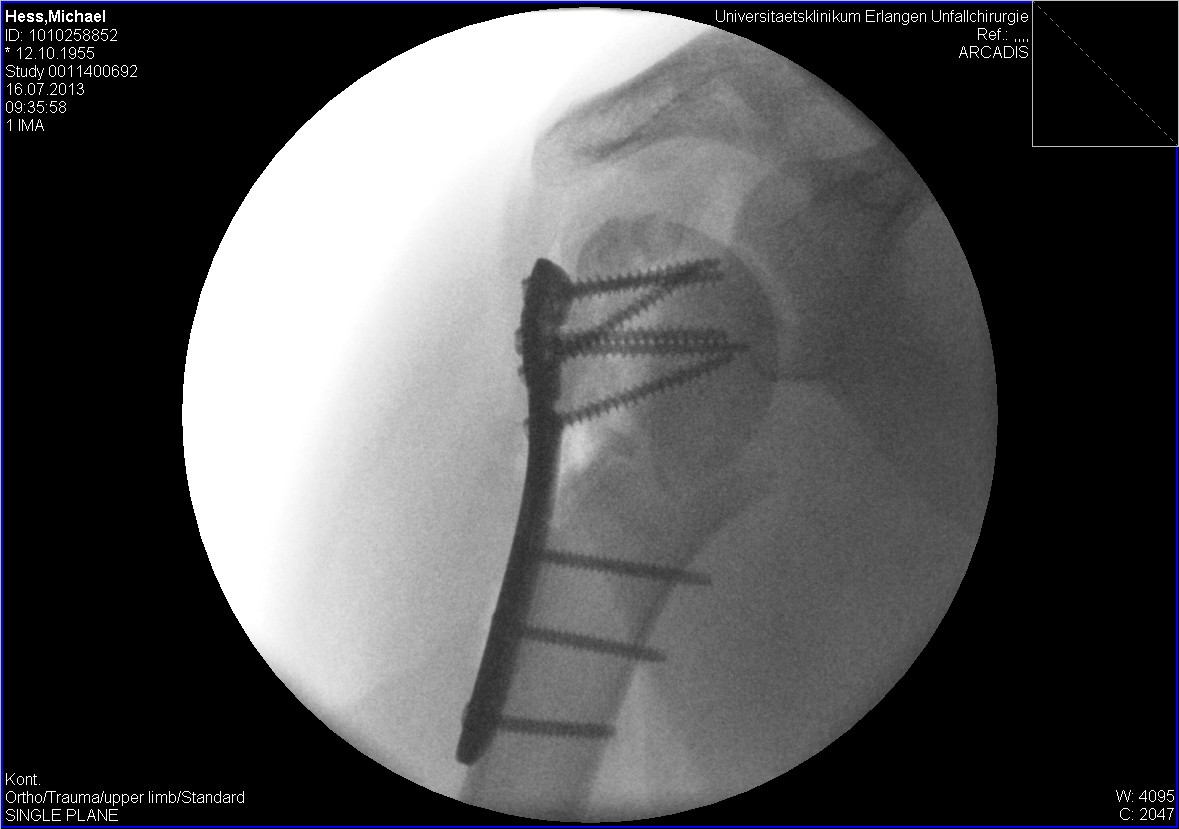

Meine rechte Schulter sieht im Moment so aus direkt nach der OP...

Zu deiner Schulter kann ich dir aber sagen das du auf alle Fälle regelmäßig ein Röntgenbild bzw MRT machen solltest. Die Durchblutung wird an der Bruchstelle extrem gestört und der Knochen kann komplett eingehen, was ich leider schon selbst erfahren musste und dann waren da plötzlich nur noch die Nägel

Zu deiner Schulter kann ich dir aber sagen das du auf alle Fälle regelmäßig ein Röntgenbild bzw MRT machen solltest. Die Durchblutung wird an der Bruchstelle extrem gestört und der Knochen kann komplett eingehen, was ich leider schon selbst erfahren musste und dann waren da plötzlich nur noch die Nägel![]()